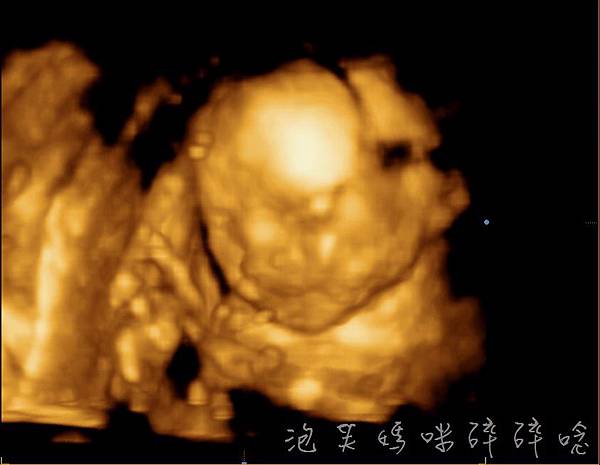

[Mommy Diary] 為寶寶紀錄生命開始那瞬間─關於泡芙的超音波照片保存☆本文被收錄於非常婚禮精華文章

[Mommy Diary] 小泡芙的高層次超音波